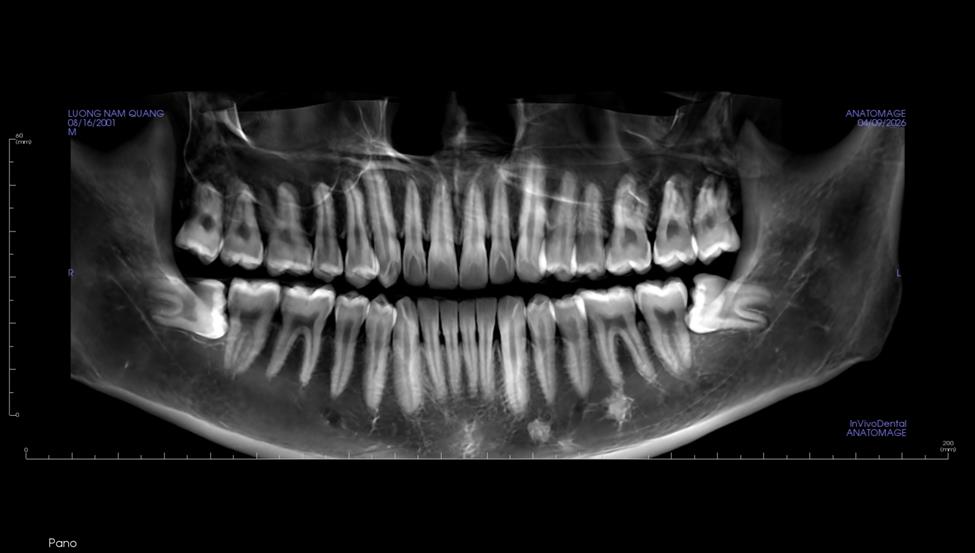

Anh Lương Quang Nam đến thăm khám trong tình trạng lo âu và chịu đựng những cơn đau nhức khó chịu kéo dài ở vùng góc hàm. Qua quá trình thăm khám lâm sàng và chụp phim X-quang, các bác sĩ đã xác định rõ tình trạng của anh Nam:

2 răng khôn (răng số 8) hàm dưới mọc ngang, đâm trực tiếp vào chân răng số 7. Đây là biến chứng cực kỳ nguy hiểm, nếu để lâu sẽ gây viêm nhiễm, xô lệch hàm và nguy cơ cao làm hỏng chiếc răng số 7 (răng nhai chức năng quan trọng nhất).

Viêm sưng và đau nhức quanh thân răng số 8.

Cao răng mức độ 2, tạo môi trường lý tưởng cho vi khuẩn sinh sôi xung quanh khu vực răng mọc lệch.

Hình ảnh Quý khách hàng trước khi điều trị tại nha khoa Như Ngọc